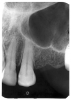

In Figure 4, recurrent caries appears at the mesial of tooth #3 and #4, and the distal of tooth #28. Also, note areas of interproximal caries on teeth #5-6.

Figure 4 - Recurrent Caries

Figure 4